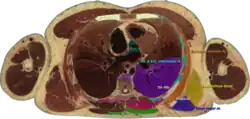

![]() Cross section #1428 of the Visible Human Male showing the structures of the triangle of auscultation | |

The superficial floor of the triangle is formed by the lateral portion of the erector spinae muscles. Deep to these muscles are the osseous portions of the 6th and 7th ribs and the internal and external intercostal muscles.

The triangle of auscultation is useful for assessment using a pulmonary auscultation and thoracic procedures.[1] Due to the relative thinning of the musculature of the back in the triangle, the posterior thoracic wall is closer to the skin surface, making respiratory sounds audible more clearly with a stethoscope. On the left side, the cardiac orifice of the stomach lies deep to the triangle. In days before X-rays were discovered, the sound of swallowed liquids were auscultated over this triangle to confirm an oesophageal tumour. To better expose the floor of the triangle up of the posterior thoracic wall in the 6th and 7th intercostal space, a patient is asked to fold their arms across their chest, laterally rotating the scapulae, while bending forward at the trunk, somewhat resembling the fetal position.